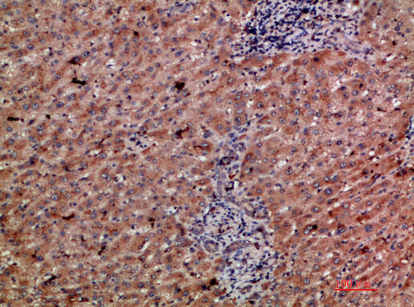

Immunohistochemical analysis of paraffin-embedded human-liver-cancer, antibody was diluted at 1:200

,